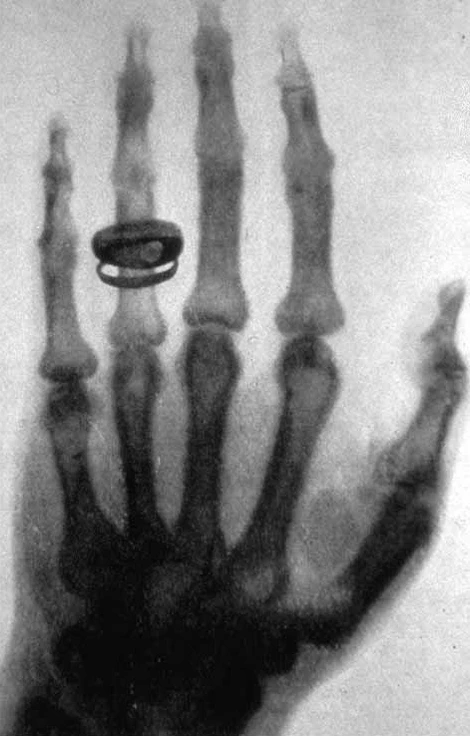

«Рука с кольцами» (нем. Hand mit Ringen) — рентегенограмма, созданная 22 декабря 1895 года немецким физиком Вильгельмом Конрадом Рентгеном. На ней запечатлена кисть левой руки жены учёного — Анны Берты Людвиг, на одном из пальцев выделяется пара колец. Снимок способствовал популяризации открытого её мужем нового вида излучения — X-лучей. 1 января 1896 года Рентген направил копию своего доклада об открытии и несколько других снимков европейским учёным, посредством чего о сенсационных опытах узнал весь мир. «Рука с кольцами» считается первым в истории медицины рентгеновским снимком человеческого организма, одной из самых влиятельных и известных научных фотографий в истории.

Начиная с 8 ноября Рентген всё своё время проводил в лаборатории, не говоря никому, чем он занят. Он не опубликовал первые результаты своего открытия, как это сделали бы многие учёные, а продолжал проводить опыты[5]. О его здоровье очень беспокоилась жена — Анна Берта Людвиг (Anna Bertha Ludwig;(1839—1919), на которой он женился в 1872 году. Она была на шесть лет старше его и страдала нервными расстройствами[6]. Мейер Фридман и Джеральд Фридланд в книге «Десять величайших открытий в истории медицины» писали, что Рентген решил успокоить жену и продемонстрировать то, чего он добился на протяжении нескольких недель напряжённых опытов, когда он «сделал по-настоящему великое открытие — пусть даже на первый взгляд необъяснимое и даже жутковатое»[7]. По мнению популяризатора науки Джона Дариуса, трубка Крукса, испускающая лучи находилась под столом. На него была положена левая рука Берты с двумя кольцами, на которую была помещена непроявленная сухая бромид-желатиновая фотопластинка (вероятно, производства компании Шлейсснер)[8]. Фридман и Фридланд писали, что наоборот, рука была положена на деревянную кассету с фотопластинкой, а катодная трубка находилась сверху[9]. Экспозиция проводилась от трёх до десяти минут[8]. По легенде, ознакомившись со снимком своей руки Берта воскликнула, что видит смерть. Фридман и Фридланд отметили: «Шок и изумление супруги привели Рентгена в восторг. Значит, его Х-лучи — не плод воспалённого воображения или больного рассудка, они так же реальны, как и стеклянные стенки трубки Крукса или ткань занавесок на окнах лаборатории. Тёмная тень от двух колец, оказавшихся на пути Х-лучей…, служила ещё одним доказательством реальности неизвестного излучения… Одного простого снимка кисти жены было достаточно, чтобы он понял, что сделал величайшее научное открытие»[10].

На негативе в виде выраженной тёмной тени выделяются силуэты колец, менее сильно видны тени костей кисти, затем мягкие ткани кисти руки[21]. В верхней части копий рентгенограмм, направленных Рентгеном учёным кем-то была сделана надпись Hand mit Ringen («Рука с кольцами»). Также изображение известно и под другими названиями, в частности, «Рука госпожи Рентген»[22][23]. На копиях также содержится указание на параграфы из доклада Рентгена «О новом роде лучей». В частности, на оттиске «Рука с кольцами» написано § 2 и 14[12]. В первом случае, отмечая степень проницаемости различных материалов и тел для Х-лучей, он писал: «Если держать между разрядной трубкой и экраном руку, то видны тёмные тени костей в слабых очертаниях тени самой руки»[24]. В параграфе 14 идёт речь об образовании теней в том случае, если между лучами и экраном поместить какой-либо предмет: «Я наблюдал, а частью и сфотографировал большое количество таких теневых картин, получение которых доставляет иногда совсем особого рода удовольствие. У меня есть, например, фотография тени профиля двери, разделяющей две комнаты. По одну сторону двери находилась разрядная трубка, а по другую пластинка; фотография тени костей, руки, тени проволоки, намотанной на деревянную, катушку, запертого в ящике набора разновесок, компаса, магнитная стрелка которого окружена со всех сторон металлом, куска металла, неоднородность которого делается заметной с помощью Х-лучей, и т. д.»[25].